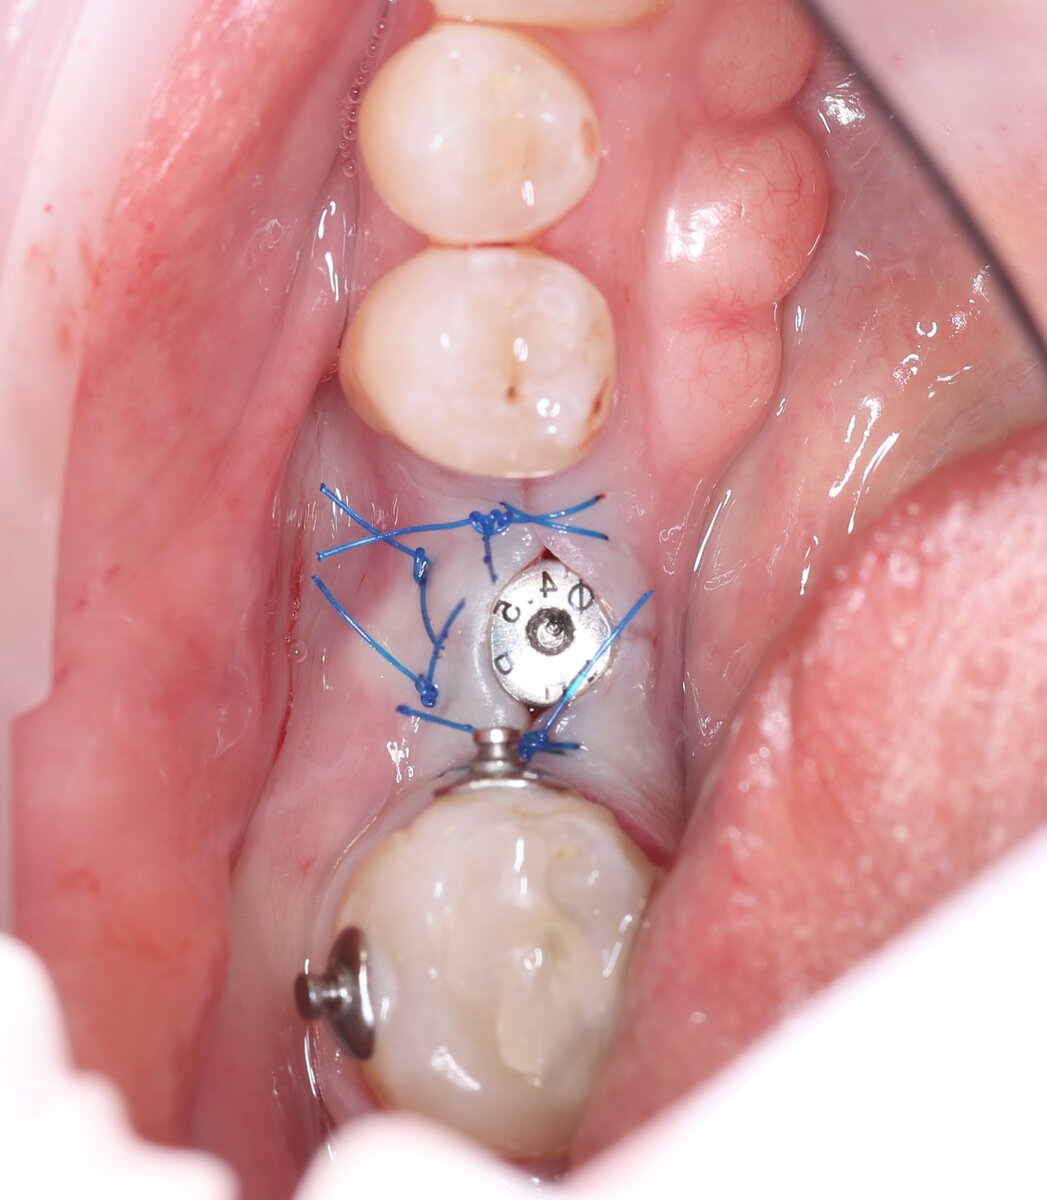

Пример. Финальное фото после немедленной имплантации. Формирователь десны виднеется из-под слизистой

При одиночных одномоментных/немедленных имплантациях в области жевательных зубах чаще это всё-таки формирователь десны.